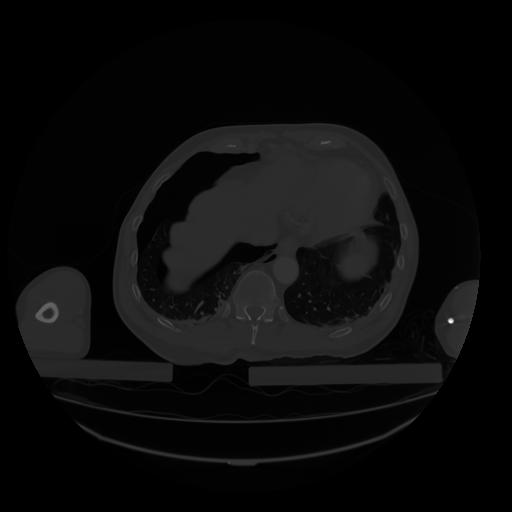

28 CUERPO,CE,Vol,2.0,CUERPO,,